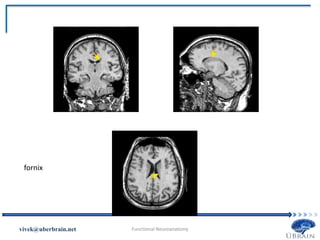

fornix

The Limbic Cortex Fornix:a bundle of axons that connects hippocampus with other regions of the brain, including the mammillary bodies (containing some of the hypothalamic nuclei) Vivek Misra